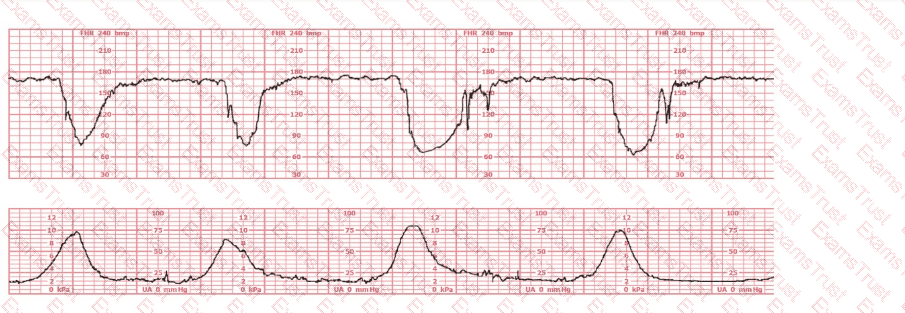

A woman has been 5 cm dilated for the past 3 hours. The tracing shown has developed over the last 30 minutes. The best initial course of action is to:

(Full question)

A 20-year-old woman (G1P0) at 40-weeks gestation was admitted for cervical ripening with dinoprostone (Cervidil) four hours ago. She developed the pattern shown one hour ago. She has been changed to a lateral position and given a fluid bolus, and the pattern continues. An appropriate intervention would be to: